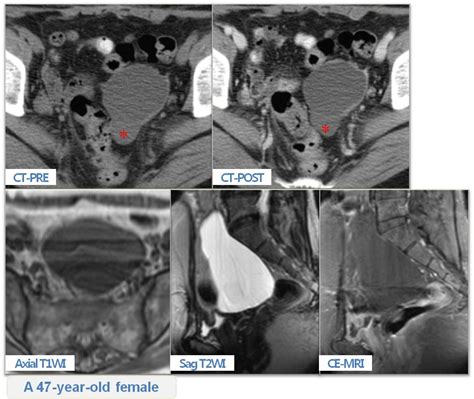

Benign multicystic mesothelioma is a rare tumour that originates from the abdominal peritoneum with a predisposition to the pelvic peritoneum. Benign tumors may grow in size but do not spread, or metastasize, to other tissues and organs. Benign mesothelioma is rarer than the malignant form, leading to a limited number of cases. In most cases, the outlook with benign tumors is very. Dabska tumor arising in lymphangioma circumscriptum // journal of cutaneous pathology. Alterations of specific tumor suppressor genes in mesothelioma. Benign mesothelioma requires treatment because the tumor may cause pressure damage on adjacent organs and because the tumor may become malignant if left alone. And persist throughout tumor progression.